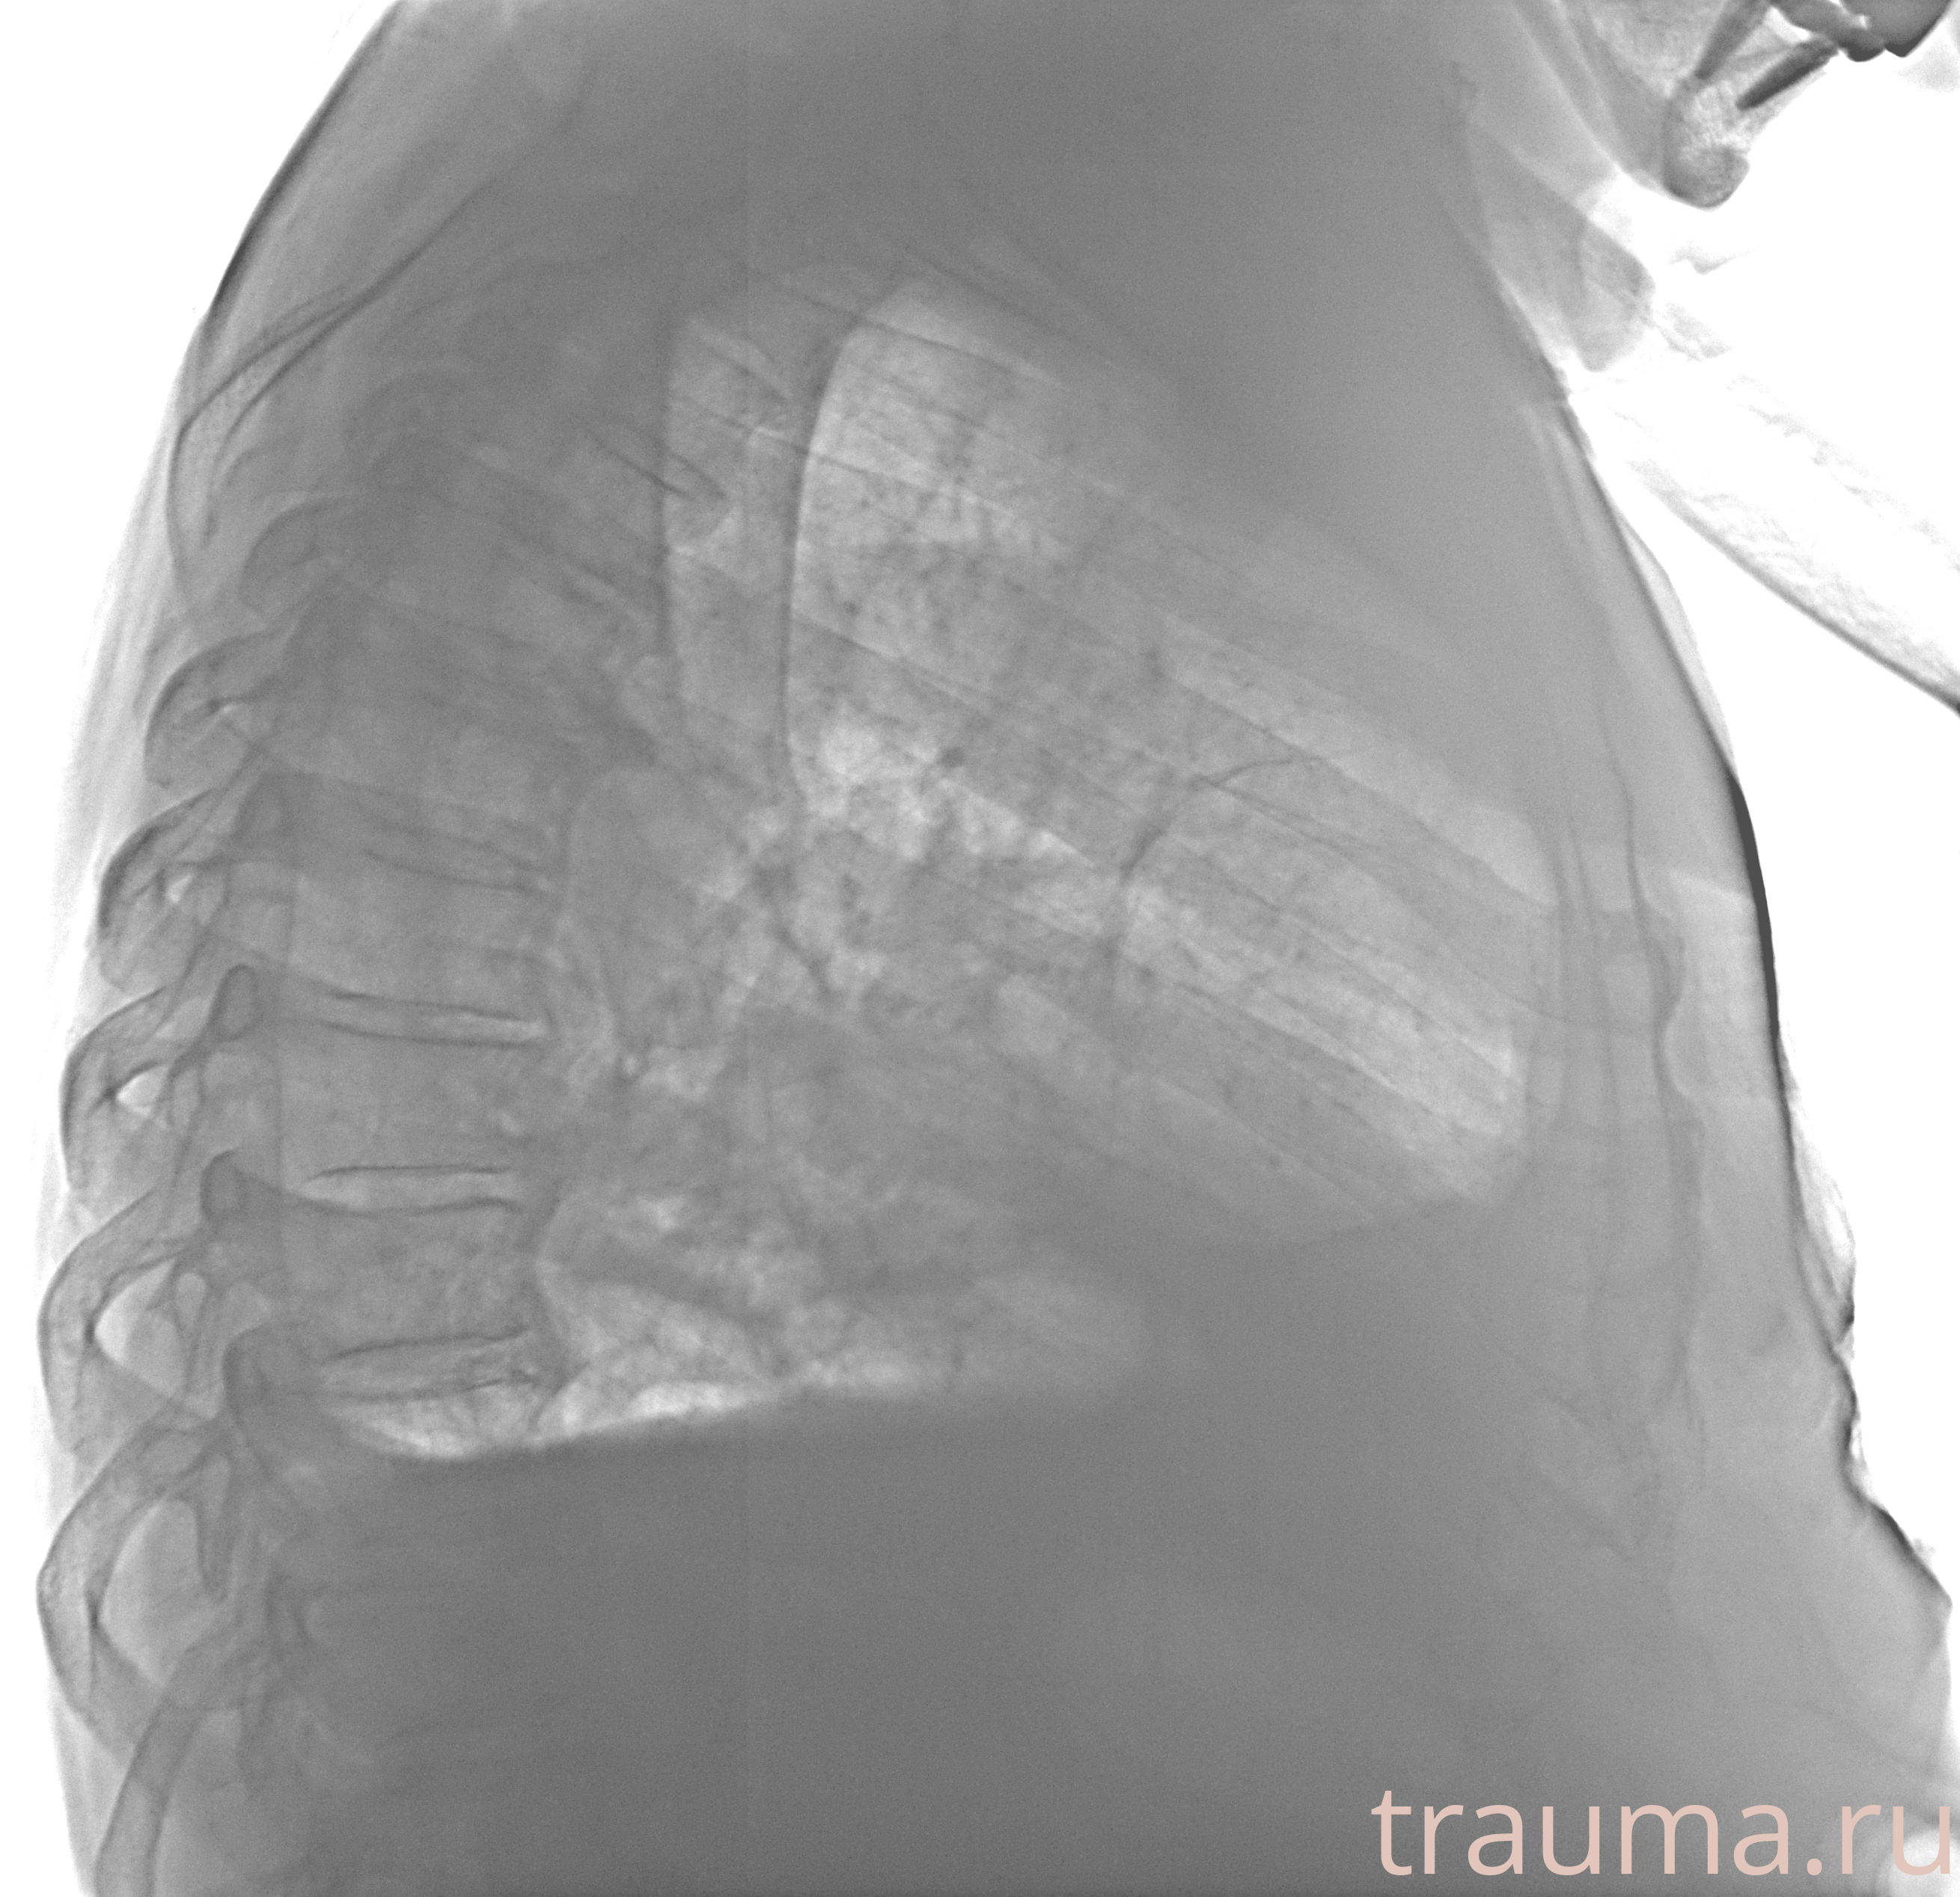

Рентген на дому: по вашему адресу приезжает врач-рентгенолог, травматолог-ортопед с мобильным рентгеновским аппаратом, проводит диагностику травмы или заболевания, делает необходимые рентгенограммы, дает рекомендации по дальнейшему лечению. Получить качественные снимки в домашних условиях возможно благодаря уникальной методике, разработанной МосРентген Центром для института  Склифосовского